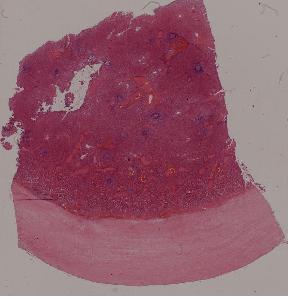

4. Hyaline degeneration of splenic capsule